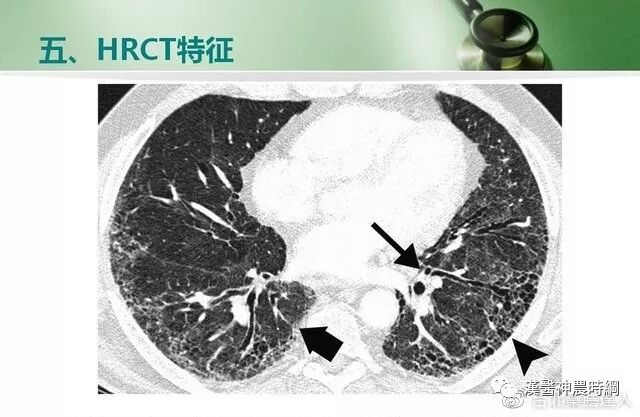

大多数间质性肺疾病都有共同的病理基础过程。初期损伤之后有肺泡炎,随着炎性-免疫反应的进展,肺纤维化泡壁、气道和血管最终都会发生不可逆的肺部瘢痕(纤维化)。炎症和异常修复导致肺间质细胞增殖,产生大量的胶原和细胞外基质。肺组织的正常结构为囊性空腔所替代,这些囊性空腔有增厚的纤维组织所包绕,此为晚期的“蜂窝肺”。肺间质纤维化和“蜂窝肺”的形成,导致肺泡气体-交换单元持久性的丧失。

一般情况下,肺纤维化早期出现肺泡炎,肺泡内有浆液和细胞成分,肺间质内有大量单核细胞,部分淋巴细胞,浆细胞,肺泡巨噬细胞等炎性细胞浸润,肺泡结构完整。进入晚期,慢性炎症已减轻,肺泡结构为坚实的胶原代替,肺泡壁被破坏,形成扩张的蜂窝肺。胶原、细胞外基质、成纤维细胞分布在间质中,肺泡上皮化生为鳞状上皮。基于以上病理变化,临床上多表现为进行性呼吸困难或伴有刺激性干咳,胸部X线显示两中下肺野网状阴影,肺功能为限制性通气功能障碍。病情呈持续性进展,最终因呼吸衰竭而死亡。

早期虽有呼吸困难,但X线胸片可能基本正常;中后期出现两肺中下野弥散性网状或结节状阴影,偶见胸膜腔积液,增厚或钙化。肺组织纤维化的严重后果,导致正常肺组织结构改变,功能丧失。就是大量没有气体交换功能的纤维化组织代替肺泡,导致氧不能进入血液。患者呼吸不畅,缺氧、酸中毒、丧失劳动力、靠呼吸机生存,最后衰竭、死亡。